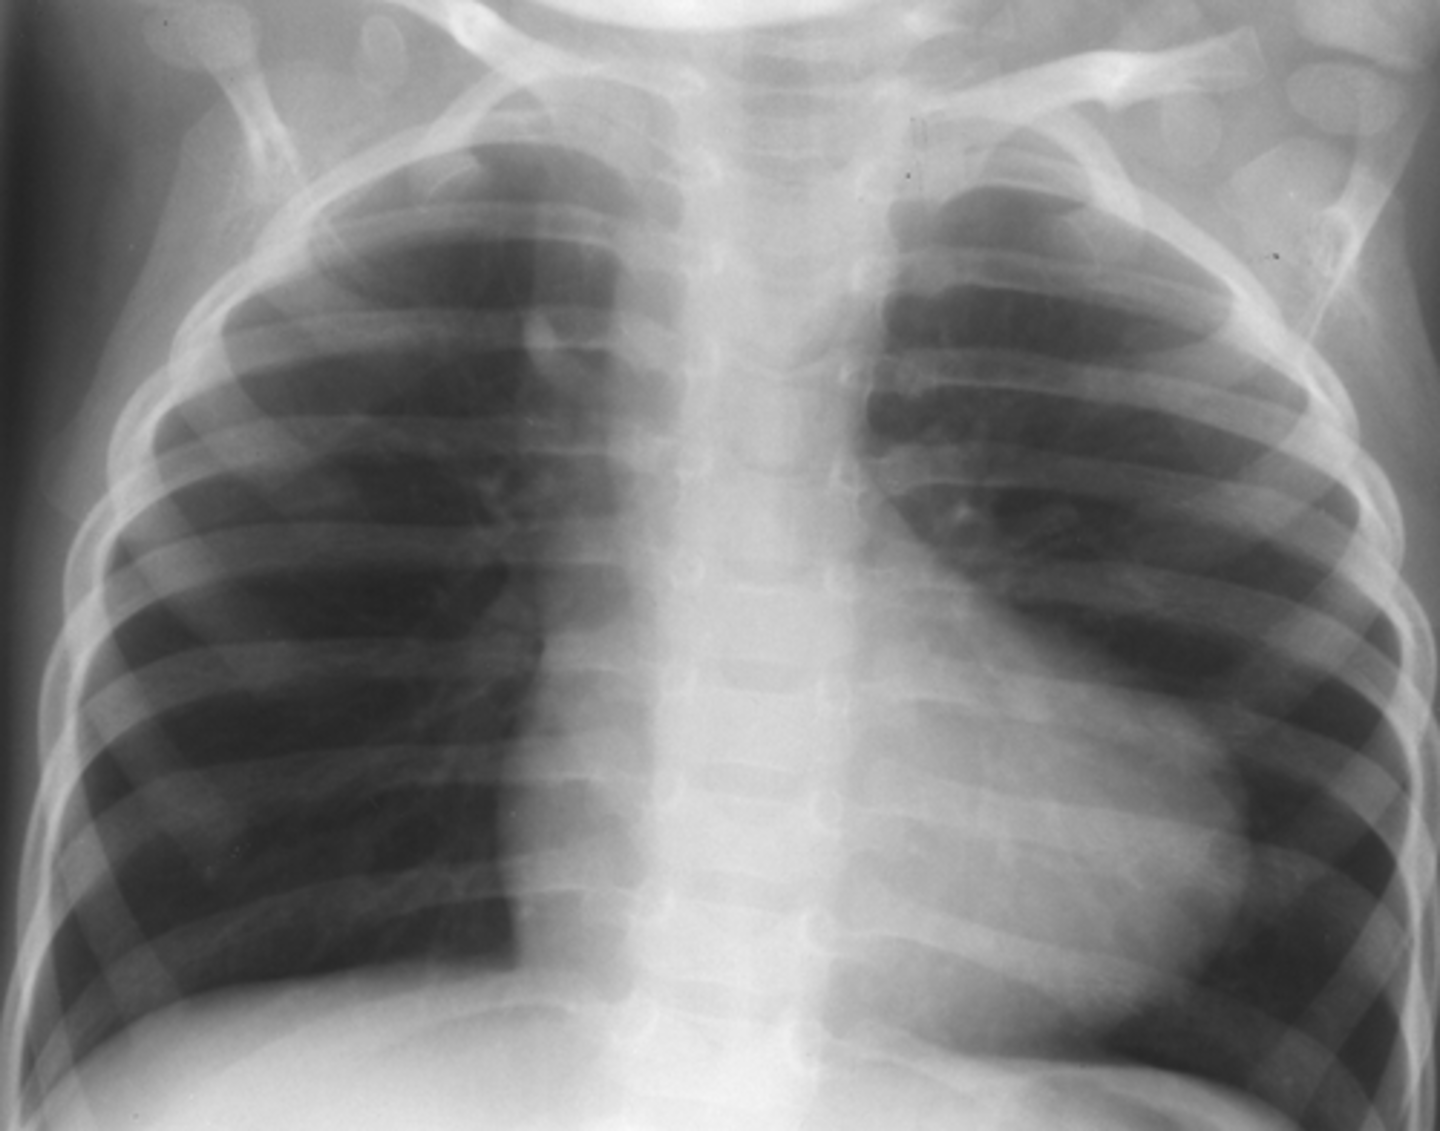

What are 2 characteristic CXR signs of coarctation of the aorta?

Figure 3 sign; inferior notching of the ribs